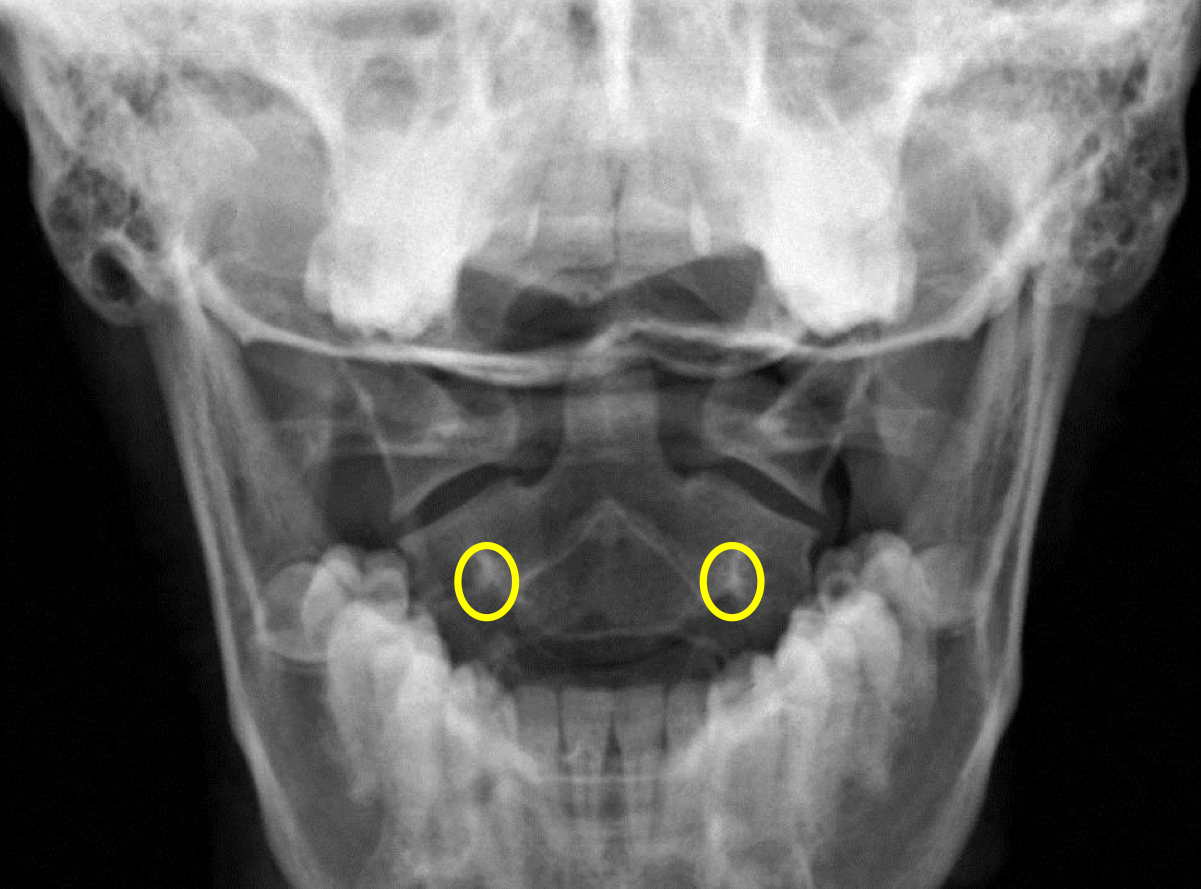

What view is this?

APOM

What is this?

C1 Lateral Masses

What is this?

C2 Pedicle Shadows